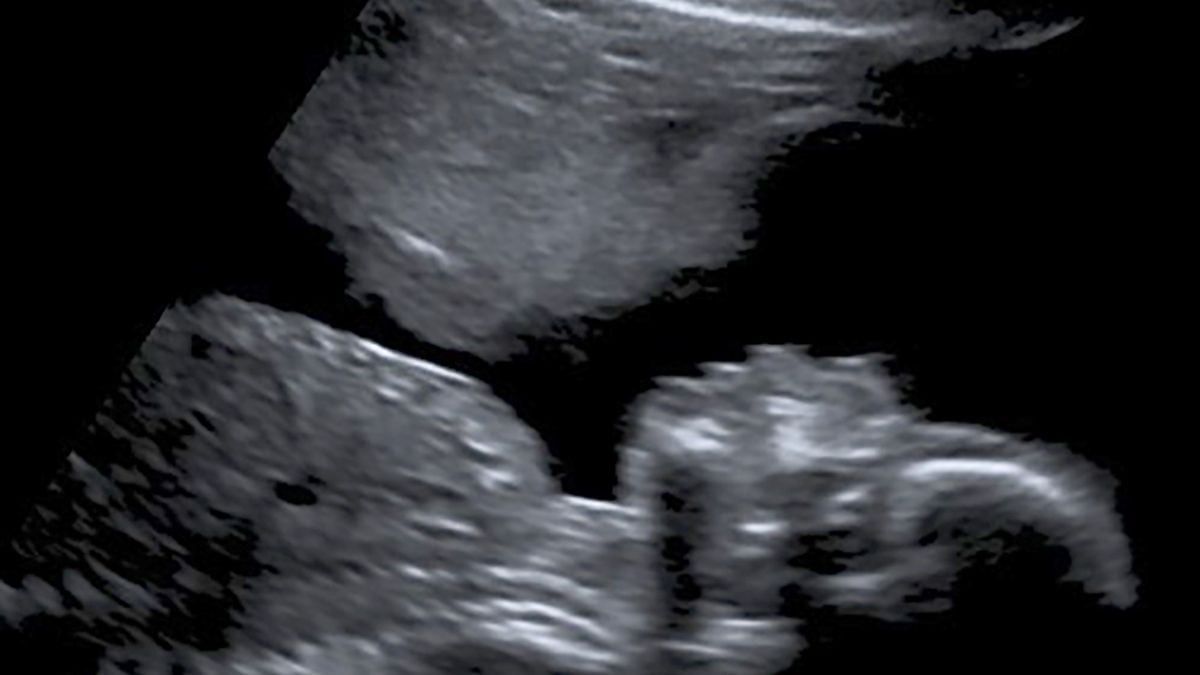

Afortunadamente, el panorama comenzó a cambiar paulatinamente: dejó de sangrar a las 19 semanas y en la eco de las 20 semanas la imagen reveló algo junto al bebé en gestación, que la mujer definió como el ‘ángel de la guarda’: “No estaba fuera de peligro, pero definitivamente podía respirar un poco más”.